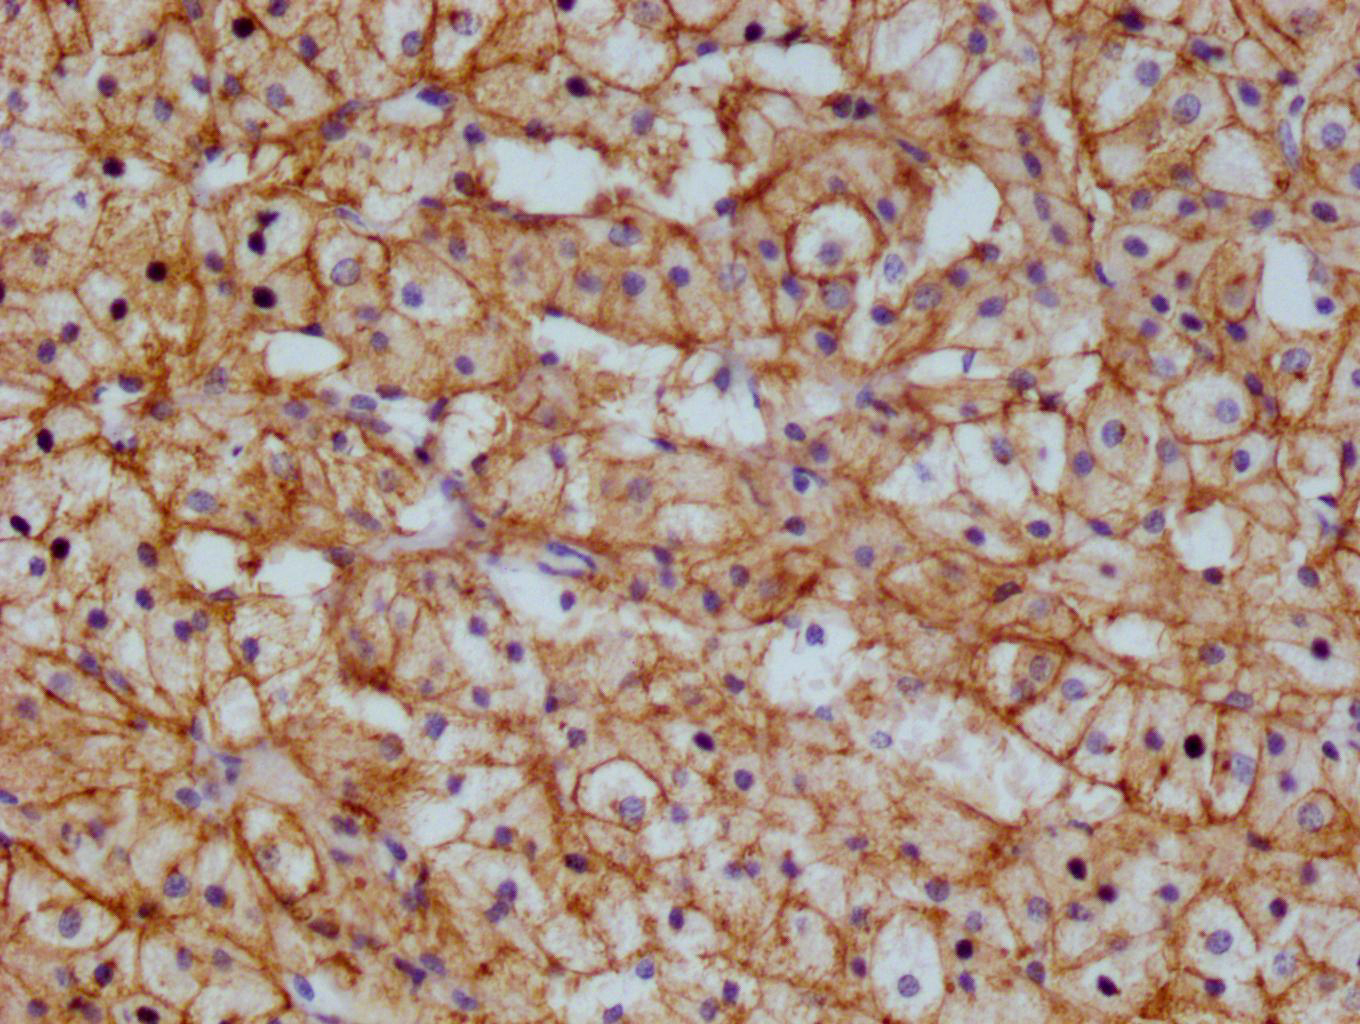

IHC image of CSB-RA983422A0HU diluted at 1:100 and staining in paraffin-embedded human adrenal gland tissue performed on a Leica BondTM system. After dewaxing and hydration, antigen retrieval was mediated by high pressure in a citrate buffer (pH 6.0). Section was blocked with 10% normal goat serum 30min at RT. Then primary antibody (1% BSA) was incubated at 4°C overnight. The primary is detected by a Goat anti-rabbit polymer IgG labeled by HRP and visualized using 0.05% DAB.

ApplicationsImmunoFluorescence, ELISA, ImmunoHistoChemistry

- ApplicationsImmunoFluorescence, ELISA, ImmunoHistoChemistry